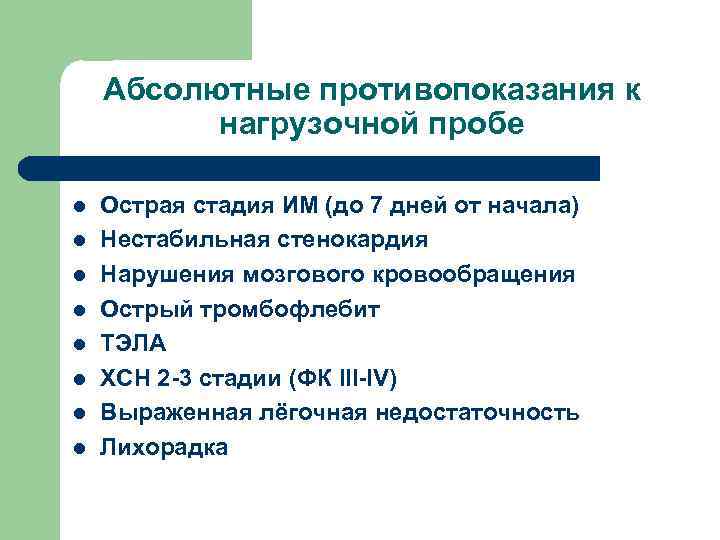

Абсолютные противопоказания к нагрузочной пробе l l l l Острая стадия ИМ (до 7 дней от начала) Нестабильная стенокардия Нарушения мозгового кровообращения Острый тромбофлебит ТЭЛА ХСН 2 -3 стадии (ФК III-IV) Выраженная лёгочная недостаточность Лихорадка